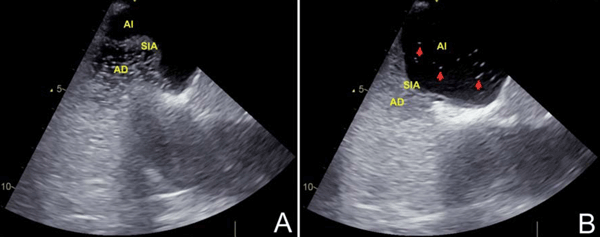

El ecocardiograma transtorácico (ETT) es usualmente la primera modalidad de imagen realizada. Con la imagen armónica se ha reportado una sensibilidad de 91% y una especificidad de 93% para el diagnóstico de FOP7. A pesar de esto, existen inconsistencias entre los estudios y un bajo nivel de evidencia para los criterios diagnósticos. Es necesario el uso de contraste para demostrar el cortocircuito derecha-izquierda; es diagnóstica la presencia de más de una burbuja en la aurícula izquierda dentro de los primeros tres latidos. Sin embargo, la presencia de cortocircuitos pequeños o imágenes subóptimas puede limitar su eficacia, por lo que se prefiere la modalidad de ecocardiograma transesofágico (ETE) (figura 1). El Doppler color en el ETE ha registrado una sensibilidad y especificidad de 100% para detectar FOP8. La academia estadounidense de neurología recomienda realizar ETE con contraste para detectar FOP y cortocircuito interauricular en el escenario agudo del ictus9. El ultrasonido Doppler transcraneal con contraste puede detectar un cortocircuito de derecha a izquierda, pero tiene dificultades para ubicar su localización, por lo que puede ser usado en conjunto con el ETT y el ETE, para mejorar la precisión diagnóstica10. Debido al bajo nivel de la evidencia, ningún estudio es considerado de elección, y en la mayoría de los casos el diagnóstico preciso de FOP necesita aunar los aportes de diferentes técnicas6.

Figura 1: Ecocardiograma transesofágico: en la imagen A se observa la aurícula derecha (AD) con suero salino agitado. En la imagen B se aprecia el paso de burbujas (señaladas por las flechas) a la aurícula izquierda (AI). Al comparar las imágenes destaca la excursión desde la línea media mayor a 10 mm del septum interauricular (SIA).

Algunas características estructurales podrían predecir el riesgo de recurrencias de IC en pacientes con FOP. Estas características, que deben buscarse con detenimiento en el ETE, son el ASIA y el tamaño del FOP. El ASIA, cuya definición varía en los diferentes estudios, de forma general se refiere a la excursión del septum interauricular ³10 mm desde la línea media. El tamaño del FOP se describe en base al cortocircuito derecha-izquierda, definido por el número de burbujas en la aurícula izquierda en menos de tres latidos cardíacos luego de la opacificación de la aurícula derecha con suero salino agitado. Aunque el número de burbujas usado para definir el tamaño varía de un estudio a otro, la mayoría de los autores usa un punto de corte de más de 10 burbujas6,11. El estudio CLOSE12 usó un número de más de 30 burbujas para definir un FOP como amplio, reportando que la recurrencia de IC en el grupo sin cierre percutáneo fue de 12,2% en los pacientes con ASIA y cortocircuito amplio, mientras que fue de 3,1% en los pacientes con FOP amplio sin ASIA.